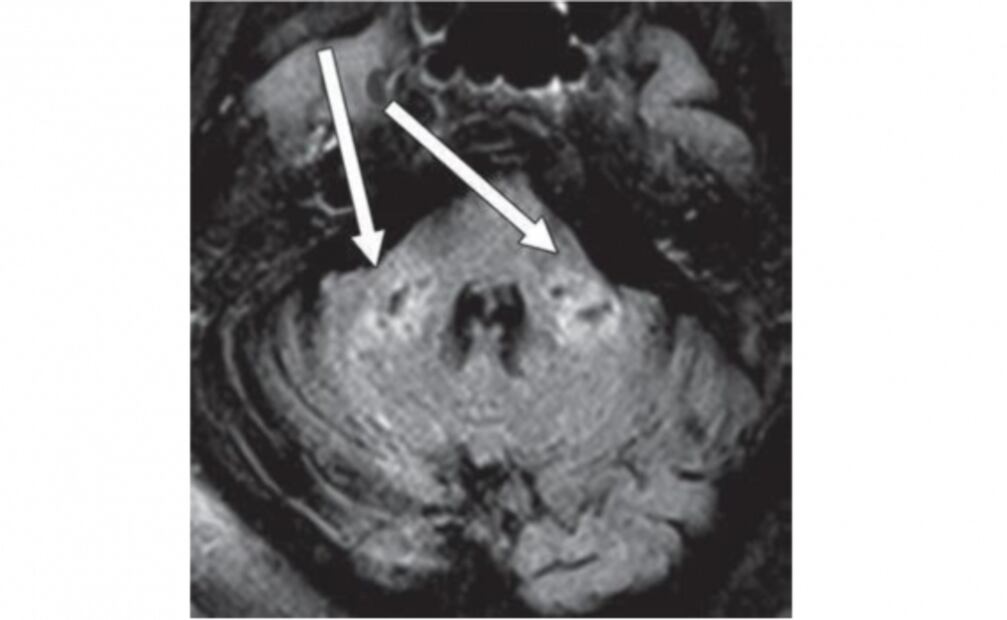

Del 1 de marzo al 18 de junio de 2020, el equipo de expertos estudió a 2 mil 820 pacientes con Covid-19 que ingresaron al centro hospitalario, algunos de ellos incluso se sometieron a realizarse una resonancia magnética cerebral, donde se pudo observar la leucoencefalopatía diseminada.

Foto: American Roentgen Ray Society (ARRS), American Journal of Roentgenology (AJR)